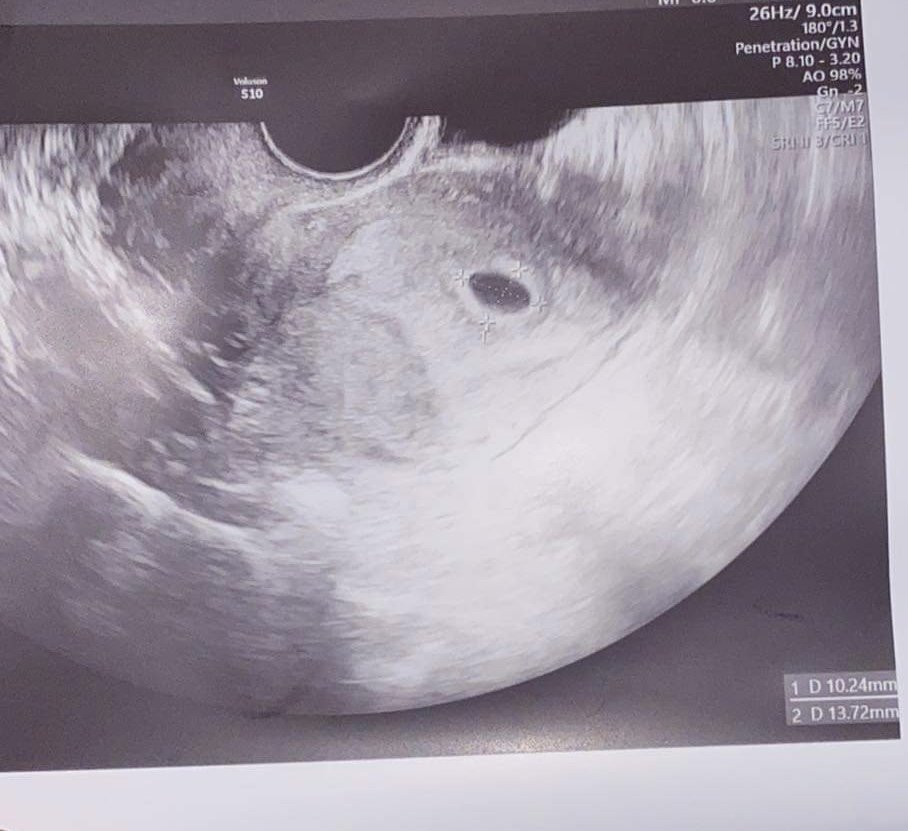

Майките споделят различни симптоми на бременност, като болезнени и подути гърди, гадене, стомашни болки, умора, замаяност, болки в кръста, наддаване на тегло в областта на корема , сутрешно гадене , повишена чувствителност на гърдите и повишена сънливост. Важно е да се отбележи обаче, че симптомите на бременността могат да варират значително между отделните жени. Някои от споделените симптоми включват гадене, често уриниране през нощта, умора, чувствителност и напрежение в гърдите, киселини в стомаха, главоболие и промени в обонянието. Важно е да се отбележи обаче, че симптомите на бременността могат да варират значително от жена до жена. Хората във форума споделят различни симптоми на бременност като гадене, повръщане, киселини, болезнени гърди, главоболие, умора, запек , повишен апетит , увеличен обем на корема , кафяво течение , умора и чувство на напрежение в корема. Жените в бременност често изпитват различни симптоми като главоболие, гадене, умора и промени в настроението поради хормони. Те могат също да изпитат физически дискомфорт като подуване, коремна болка и различни зацапвания. Тези усещания понякога могат да бъдат стресиращи и тревожни относно здравето на плода. Въпреки това, много жени намират успокоение от редовните медицински прегледи и уверенията, че бебето е добре.